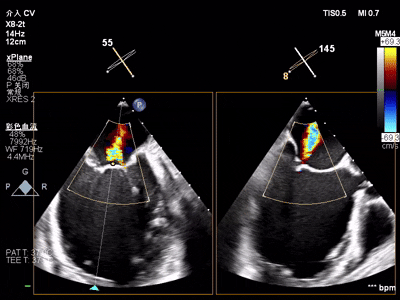

【术前超声心动图提示】

室性功能性二尖瓣反流(混合性MR),重度(MR 5+),反流位于2区–3区,左室射血分数低(EF27%)

【瓣膜与功能特点】

前超声评估明确关键指标:二尖瓣瓣环呈扩张状态(前后径约3.3cm,瓣环面积约4.75cm²,前叶长约2.1 cm,后叶长约1.4 cm),瓣叶增厚且后叶栓系明显,前后叶对合不良;同时伴左房、左室明显扩大,左室收缩功能显著减低,合并节段性运动异常。经团队综合评估,该患者为“多支冠脉支架植入后+低射血分数+重度功能性二尖瓣反流(混合性MR)”的高危病例,左室射血分数(EF)仅20%,在接受GDMT药物优化治疗6周后EF值提升至27%,但症状仍无法有效缓解,遂决定为其实施经心尖入路二尖瓣缘对缘修复术(TA-TEER)。